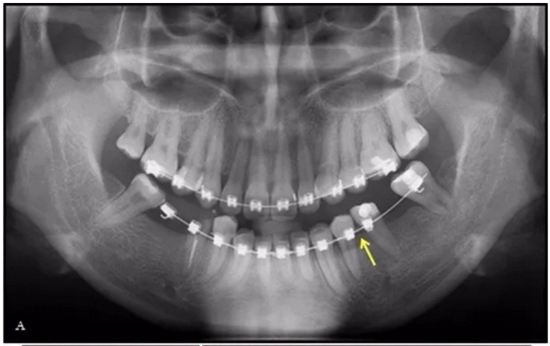

36歲;女性;尋求下頜左后方區(qū)域間隙管理的建議(圖1和圖2),通過治療獲得了良好的牙頜面效果(圖3和圖4)。她被診斷患有骨性I類和代償性牙性II類錯合畸形,并且上頜左側(cè)尖牙缺失(圖1和2)。大約七年前,由于不可修復(fù)的齲齒,拔除了下頜左側(cè)第一和第二磨牙(圖5)。37相鄰的第三磨牙向近中移動并傾斜入間隙,導致無牙頜間隙減小至約14 mm(圖2和圖5)。臨床和影像學評估顯示多發(fā)性齲損和在下頜右側(cè)567處有一不良的固定橋修復(fù)體(圖1和5)。此外,下頜左中切牙缺失,造成下頜中線向左側(cè)偏移約3 mm(圖1和圖2)?;颊咦栽V,她的右上第一前磨牙和左上尖牙在13歲時由其家庭牙醫(yī)拔除,因為它們被阻塞到頰側(cè)萌出(圖1)。上頜第二磨牙缺失(未知病因),并且相鄰的第三磨牙已經(jīng)轉(zhuǎn)移到第二磨牙間隙中。如補充材料所示,美國正畸學差異指數(shù)DI是28分。種植體部位(下頜左側(cè)和右側(cè)第一磨牙)由于復(fù)雜性得到額外4分(補充材料)。

總之,這種復(fù)合錯合畸形是一個很嚴重的問題,需要進行認真的多學科序列治療。治療后X光片(圖6)和重疊頭影測量圖(圖7)記錄了跨學科治療結(jié)果。

成人正畸患者通常有缺牙和牙槽骨萎縮。假設(shè)相鄰的牙齒是牙周健康的,可以通過正畸牙齒移動擴大狹窄的牙脊。該過程是通過牙周膜牽引以產(chǎn)生束骨:骨內(nèi)礦化的膠原束(Sharpey's纖維)。當牙根表面與萎縮牙槽骨的致密骨皮質(zhì)接觸時,牙根側(cè)面吸收是常見的。使用輕力使下頜前磨牙的平移可減少牙周膜壞死和牙根側(cè)面吸收,但這也大大提高了牙齒移動的速度。當牙齒之間的間隙被打開形成種植位置時,新形成的牙槽嵴主要是未成熟的束骨,并且一旦形成就開始在高度和頰側(cè)寬度上萎縮。在種植體植入時建議牙槽嵴骨移植以補償預(yù)期的額外骨質(zhì)流失。強烈建議使用固定保持器進行間隙保持,直到種植體支持式修復(fù)體的完成。盡管在種植體部位出現(xiàn)骨和軟組織問題,但獲得了極好的總體結(jié)果,差異指數(shù)DI(模型頭測評估)從28分降到了13分。